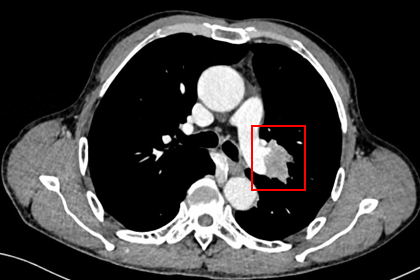

胸部CT显示左侧上叶支气管旁部发现一不规则、边界不清的软组织肿块,大小约为41mm×26mm。增强扫描后,肿瘤呈显著不均匀强化,与肿大的淋巴结粘连且难以区分,部分包裹左上叶支气管,导致管腔狭窄。左上叶肺叶间裂增厚,多个结节灶提示可能存在肺内转移。

治疗缓解评估:影像学(CT)显示原发肿瘤及叶间淋巴结明显缩小;支气管镜显示左上叶开口通畅,原肿块显著退缩,可见白色坏死组织;疗效评估为PR。